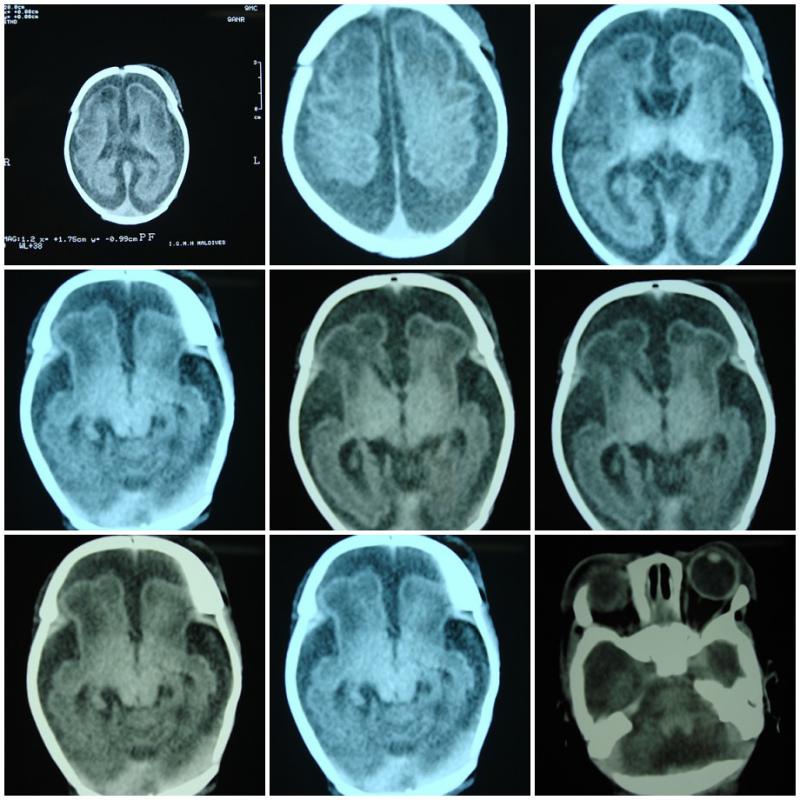

Alt beyin, insan beyninin alt bölümlerinden biri olarak, temel hayati işlevlerin düzenlenmesine katkıda bulunur. Bu bölüm, özellikle otomatik ve hayati tepkilerin kontrolünde önemli bir rol oynamaktadır. Bu makalede, alt beynin özellikleri, işlevleri ve sağladığı faydalar detaylı bir şekilde ele alınacaktır. Alt Beyinin Yapısı ve Fonksiyonları Alt beyin, beyin sapı ve limbik sistem gibi bölümleri içermektedir. Bu yapıların işlevleri arasında şunlar yer almaktadır: